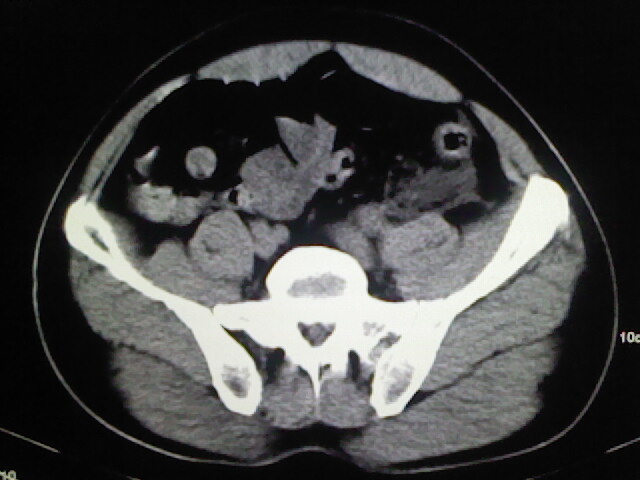

以下是引用zsl6918在2009-2-7 7:29:00的发言:[br]请提供介入的方式方法,肾及输尿管改变考虑与介入损伤有关,漏了,尿液外渗。

以下是引用余辉在2009-2-7 8:27:00的发言:[br]可能是硬化剂烧穿囊壁进入肾盂输尿管了,尿漏。不除外介入或碎石术后合并感染[br]患者术后怀疑结石,接着就碎石了?就怀疑没有确诊吗?碎石用的什么方法?气压弹道还是体外超声?如果这样的话责任人都难找

以下是引用随光逐影在2009-2-7 8:46:00的发言:[br]支持3楼意见。[br]另:不排除左肾及肾周感染可能。